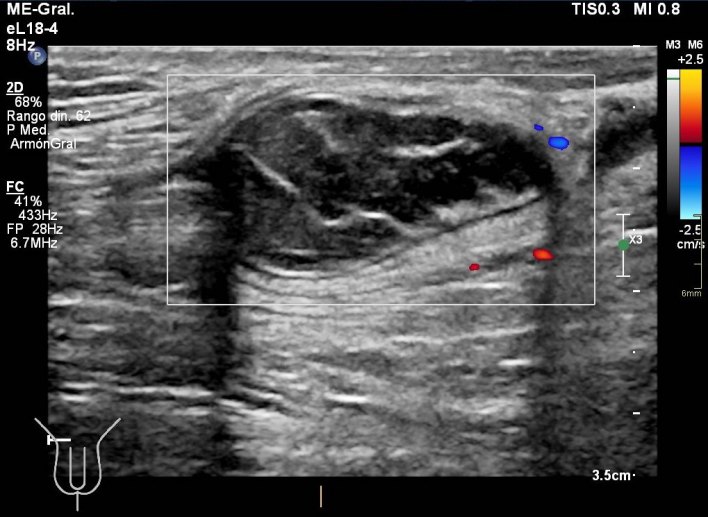

291. Lipoma de cordón y hernia inguinal.

En algunas ocasiones te encuentras cosas muy chulas, sin esperarlas, son esas cosas que no olvidas. Esta semana entró en la sala un paciente para descartar una hernia inguinal, valorada por el cirujano previa a la cirugía. Cuando el paciente se tumbó en la camilla y se descubrió la región inguinal, era evidente que algo pasaba porque tenía un bulto muy llamativo, duro. Justo cuando le puse el traductor y sin tiempo para reaccionar la hernia se corrigió, el bulto desapareció…casi. Me di cuenta que la hernia existía, sin verla, así que me pude a evaluar la región inguinal desde le teste, buscando el canal inguinal…Sorpresa…

Nada más acabar el testículo y empezar el canal inguinal me encontré una estructura hipoecogénica, con septos, con un borde ecogénico a modo de cápsula muy llamativo. La estructura era dura y fija, no respondía a valsalva, enseguida me dí cuenta de que no era parte de una hernia, no era una tripa, porque no se movía…siguiente sorpresa…

Cuando le pedía al paciente que hiciera valsalva, y por el canal inguinal aparecía una hernia muy evidente, con un cuello visible en dos proyecciones, la hernia tenía tanto grasa como asas intestinales, sonaba al entrar y al salir.

Lo más llamativo y lo que más me gustó de la prueba es que cuando la hernia llegaba a la estructura fija que estudié en primera instancia, la abrazaba, se apoyaba en ella y o conseguía moverla…y después retrocedía introduciéndose en la cavidad abdominal.

La hernia era una hernia más, el bultoma me hizo saltar las alarmas y se lo comuniqué al radiólogo responsable. Ante la sospecha razonable de que pudiera ser un tumor, decidió ampliar con un TAC de Pelvis sin CIV que demostró la existencia tumonal benigna que correspondía con un lipoma de cordón, benigno, por su aspecto amable, bordes definidos, tabique externo y centro graso.

Hernia inguinal, con foramen de 15 mm, con introduccion en saco herniario de 3 cms, de grasa omental. Imagen nodular en cordon, distal, de 2 cms, que sugiere patologia benigna.

En una misma región coexistiendo dos figuras patológicas. Fue muy bonito ver que la hernia tocaba el lipoma y retrocedía, disfruté comprobando que los hallazgos ecográficos se confirmaron con el scanner. El caso es precioso y quería que lo vieses, y en esta noche lluviosa y fría, te lo dejo en imágenes…Espero que te guste.

De la imagen 2 a la 5 puedes ver documentado y medido en dos planos con doppler la lesión fija en el cordón.

De la imagem 6 a 8 puedes ver la lesión y su relación con la hernia, en la 6, no se ve la hernia, pero sí el canal inguinal, en la 7 y la 8 observas como la hernia toca el lipoma casi abrazándolo.

La 9 demuestra el contenido de tripas en la hernia.

La 10 y la 11 como la hernia se retira paulatinamente cuando el paciente deja de hacer la maniobra de valsalva.

La imagen 12, lo que corroboraba la sospecha de lesión tumoral en el cordón a expensas de la coexistencia de una hernia en esa localización. Precioso, TODO.